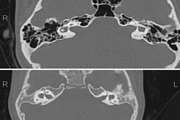

Ultrasound and magnetic resonance imaging features of fetal urogenital anomalies: A pictorial essay Jul 15 2025 - 10:59